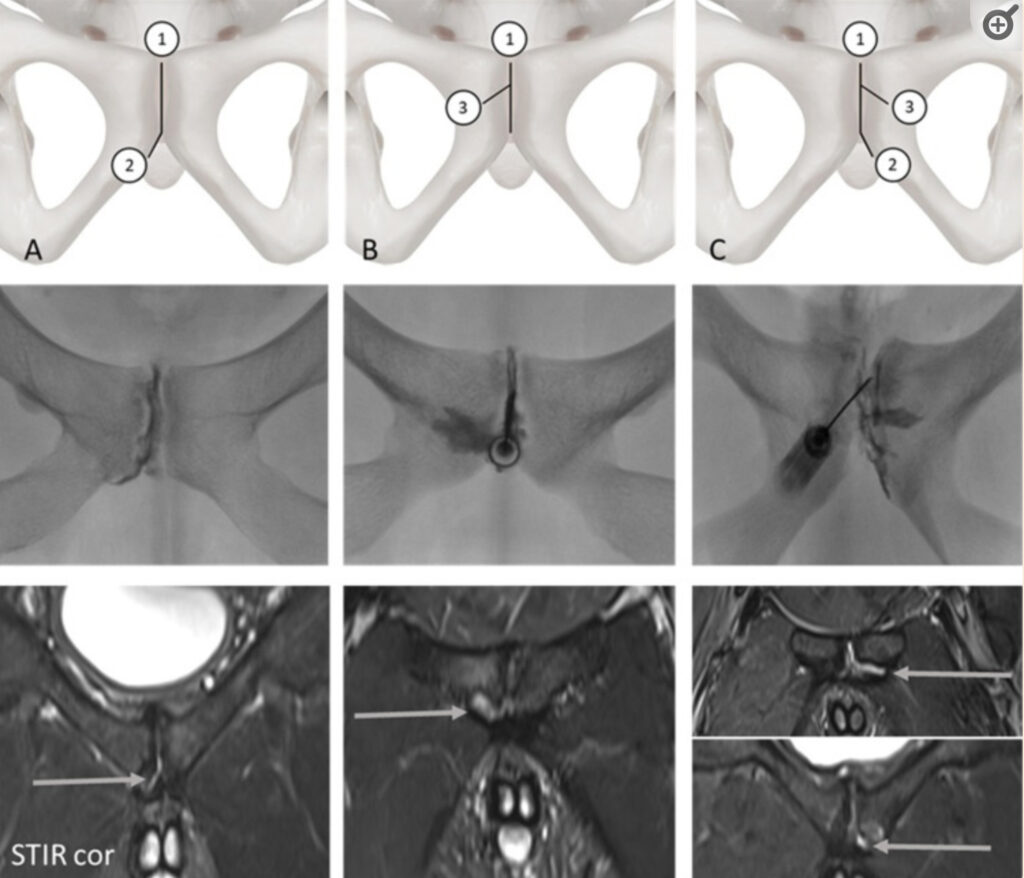

Die Zahlen kennzeichnen die physiologische Cleft (1) sowie die secondary cleft (2) oder die superior cleft (3).

Zweite Reihe Fluoroskopische Darstellung der Ceft-Verletzungen. Dritte Reihe MRT-Aufnahmen, dargestellt in einer koronaren STIR-Sequenz.Pfeile markieren Cleft-Zeichen in den MRT-Aufnahmen Spalte A: isolierte secondary cleft, Spalte B: isolierte superior cleft,

Spalte C: kombinierte Cleft-Verletzung.

Abbildung aus Holl et al, Eur Radiol. 2023; 33(10): 7321–7329